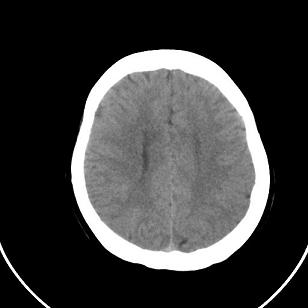

标题: CT20488:女,39岁,体检,双侧脑室有问题吗? [打印本页]

标题: CT20488:女,39岁,体检,双侧脑室有问题吗?

双侧脑室边缘呈波浪样,没有见过?

不知患者有无临床症状,双侧侧脑室边缘不规则,呈波浪状,考虑脑室周围白质软化症可能性大

影像学表现:软化灶分布于半卵圆中心和脑室周围白质,呈斑片状或长条状,多为双侧分布,脑室扩大,且脑室缘不规整。这是本症在影像学上的特点。

只有一层显示双侧侧脑室边缘不规则,呈波浪状,不排除部分容积效应,我做的话薄层再扫描一下

这个病例不符合脑室周围白质软化症

是不是应该考虑结节性硬化或者灰质移位,建议mri

1)脑灰质异位。2)双侧枕部颅骨内板下方类似扇形及弧形脑脊样低密度影;鉴别于巨大枕大池与蛛网膜囊肿之间。建议必要时行进一步检查。